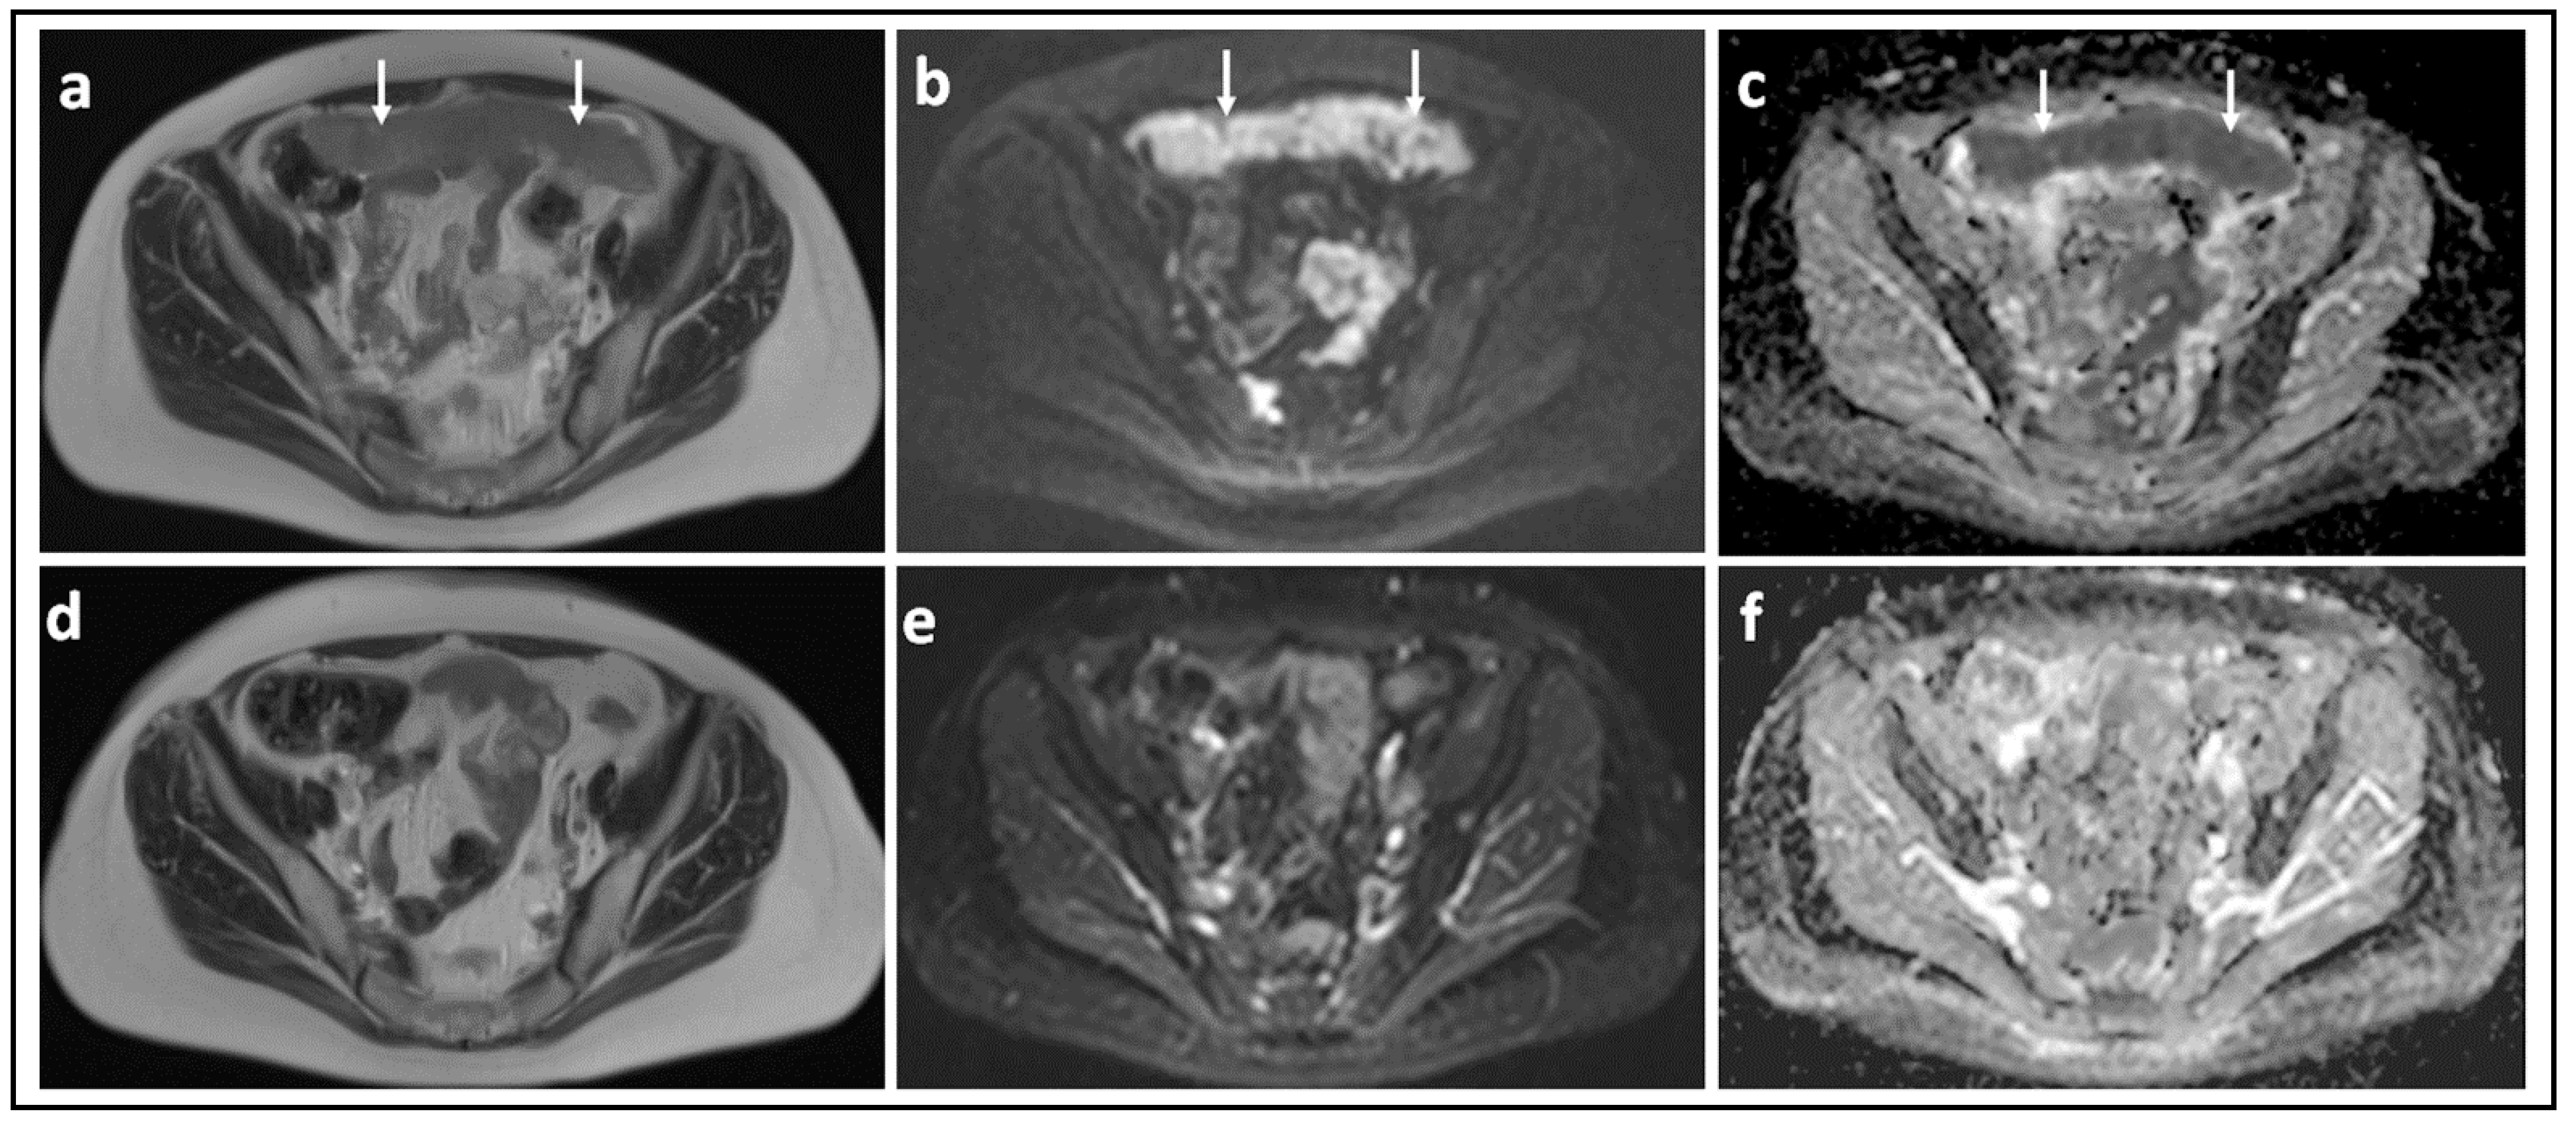

Figure 4.

Omental cake showing marked response to chemotherapy: T2-W image (a) and corresponding b = 900 s/mm2 DW-MRI (b) and ADC map (c) through the mid-pelvis in a patient with high grade serous ovarian cancer before treatment shows a large omental cake in the anterior pelvis. It is recognized by its homogenous solid appearance and marked diffusion restriction (arrows). Corresponding slices of T2-W (d), b = 900 s/mm2 DW-MRI (e) and ADC map (f) after three cycles of platinum-based chemotherapy illustrate that the omental cake is no longer identifiable.

Figure 5.

Peritoneal metastasis showing poor response to chemotherapy: T2-W image (a) and corresponding b = 900 s/mm2 DW-MRI (b) and ADC map (c) through the upper pelvis in a patient with high grade serous ovarian cancer before treatment shows an irregular right-sided peritoneal metastasis. It is recognized by its homogenous solid appearance and marked diffusion restriction [arrows]. Corresponding slices of T2-W (d), b = 900 s/mm2 DW-MRI (e) and ADC map (f) after three cycles of platinum-based chemotherapy illustrate that there has been marginal reduction in the size of this lesion.